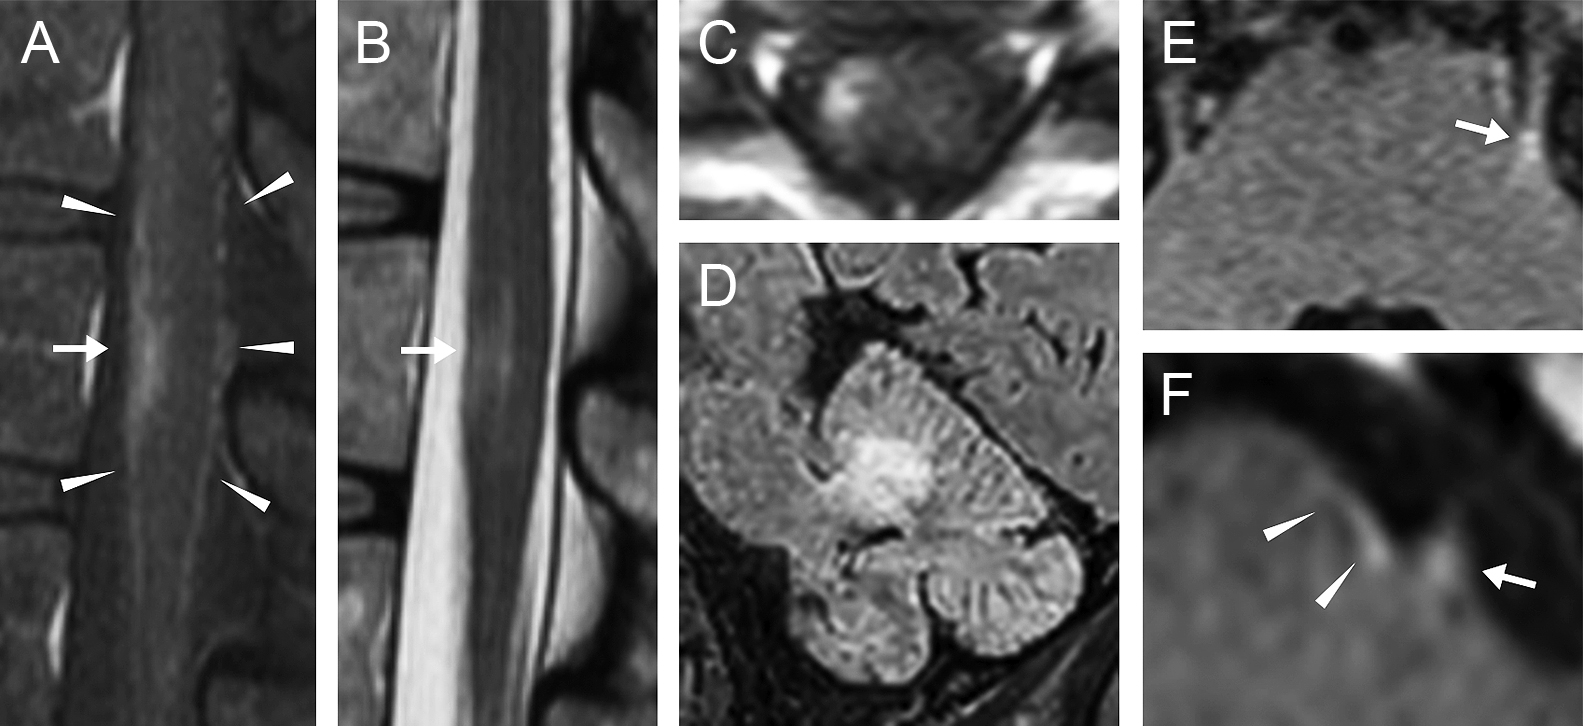

Shrimp signが診断に有用であった小脳限局型HIV関連進行性多巣性白質脳症の1例

A case of cerebellar-limited HIV-associated progressive multifocal leukoencephalopathy diagnosed with the aid of the shrimp sign

小塩 媛子, 黒田 岳志, 野原 哲人, 松岡 馨, 和田 隆秀, 村上 秀友

Himeko Ojio, Takeshi Kuroda, Tetsuhito Nohara, Kaoru Matsuoka, Takahide Wada, Hidetomo Murakami

2026/03/11